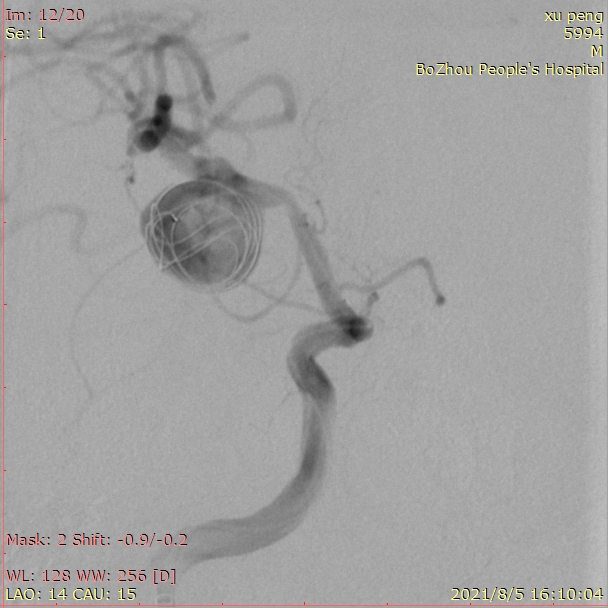

成篮圈的即刻造影和蒙片

依次填入14/30、13/30、11/30、10/20*2弹簧圈后,发现第一根微导管已经基本固定在瘤颈上方,而瘤体中心及下方仍显影明显。这时我们暂不撤回第一根微导管,然后将第二根SL-10微导管塑形后送入瘤内下方继续填圈。